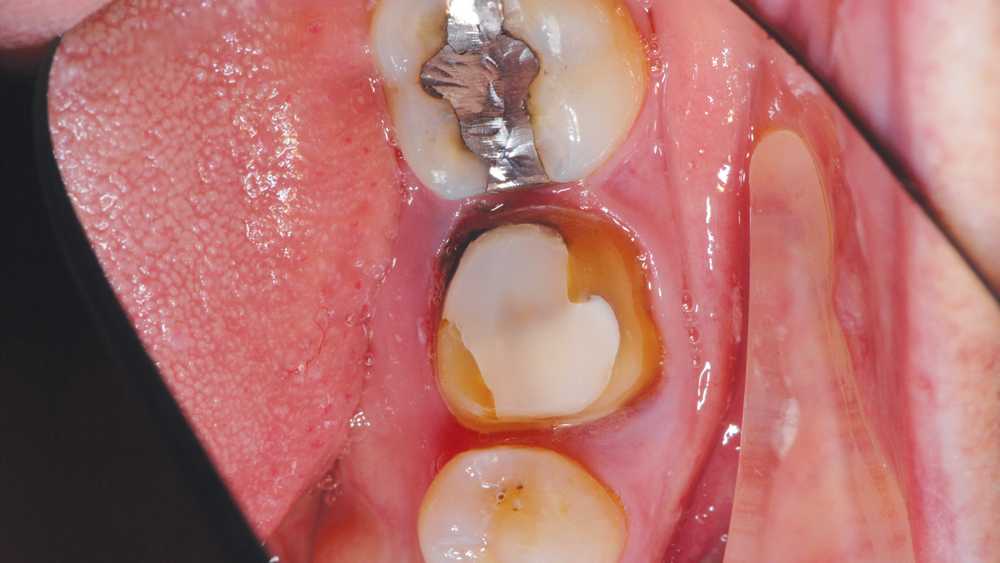

CASE REPORT

The following case highlights the efficient, user-friendly scanning capabilities of the iTero Element scanner, as well as the clinical advantages of connecting to the glidewell.io In-Office Solution for single-appointment dental restorations. The patient sought treatment for a damaged mandibular first molar with a cusp fracture. Because the case called for a single crown and high-strength zirconia, the patient was an ideal candidate for a same-visit restoration milled from a BruxZir NOW milling block. After preparing the tooth and taking an intraoral scan, the crown was fabricated within 40 minutes using the fastmill.io In-Office Unit. The final restoration fit perfectly without adjustment and exceeded the expectations of the patient, who was thrilled that she didn’t have to schedule a second appointment for the crown delivery.